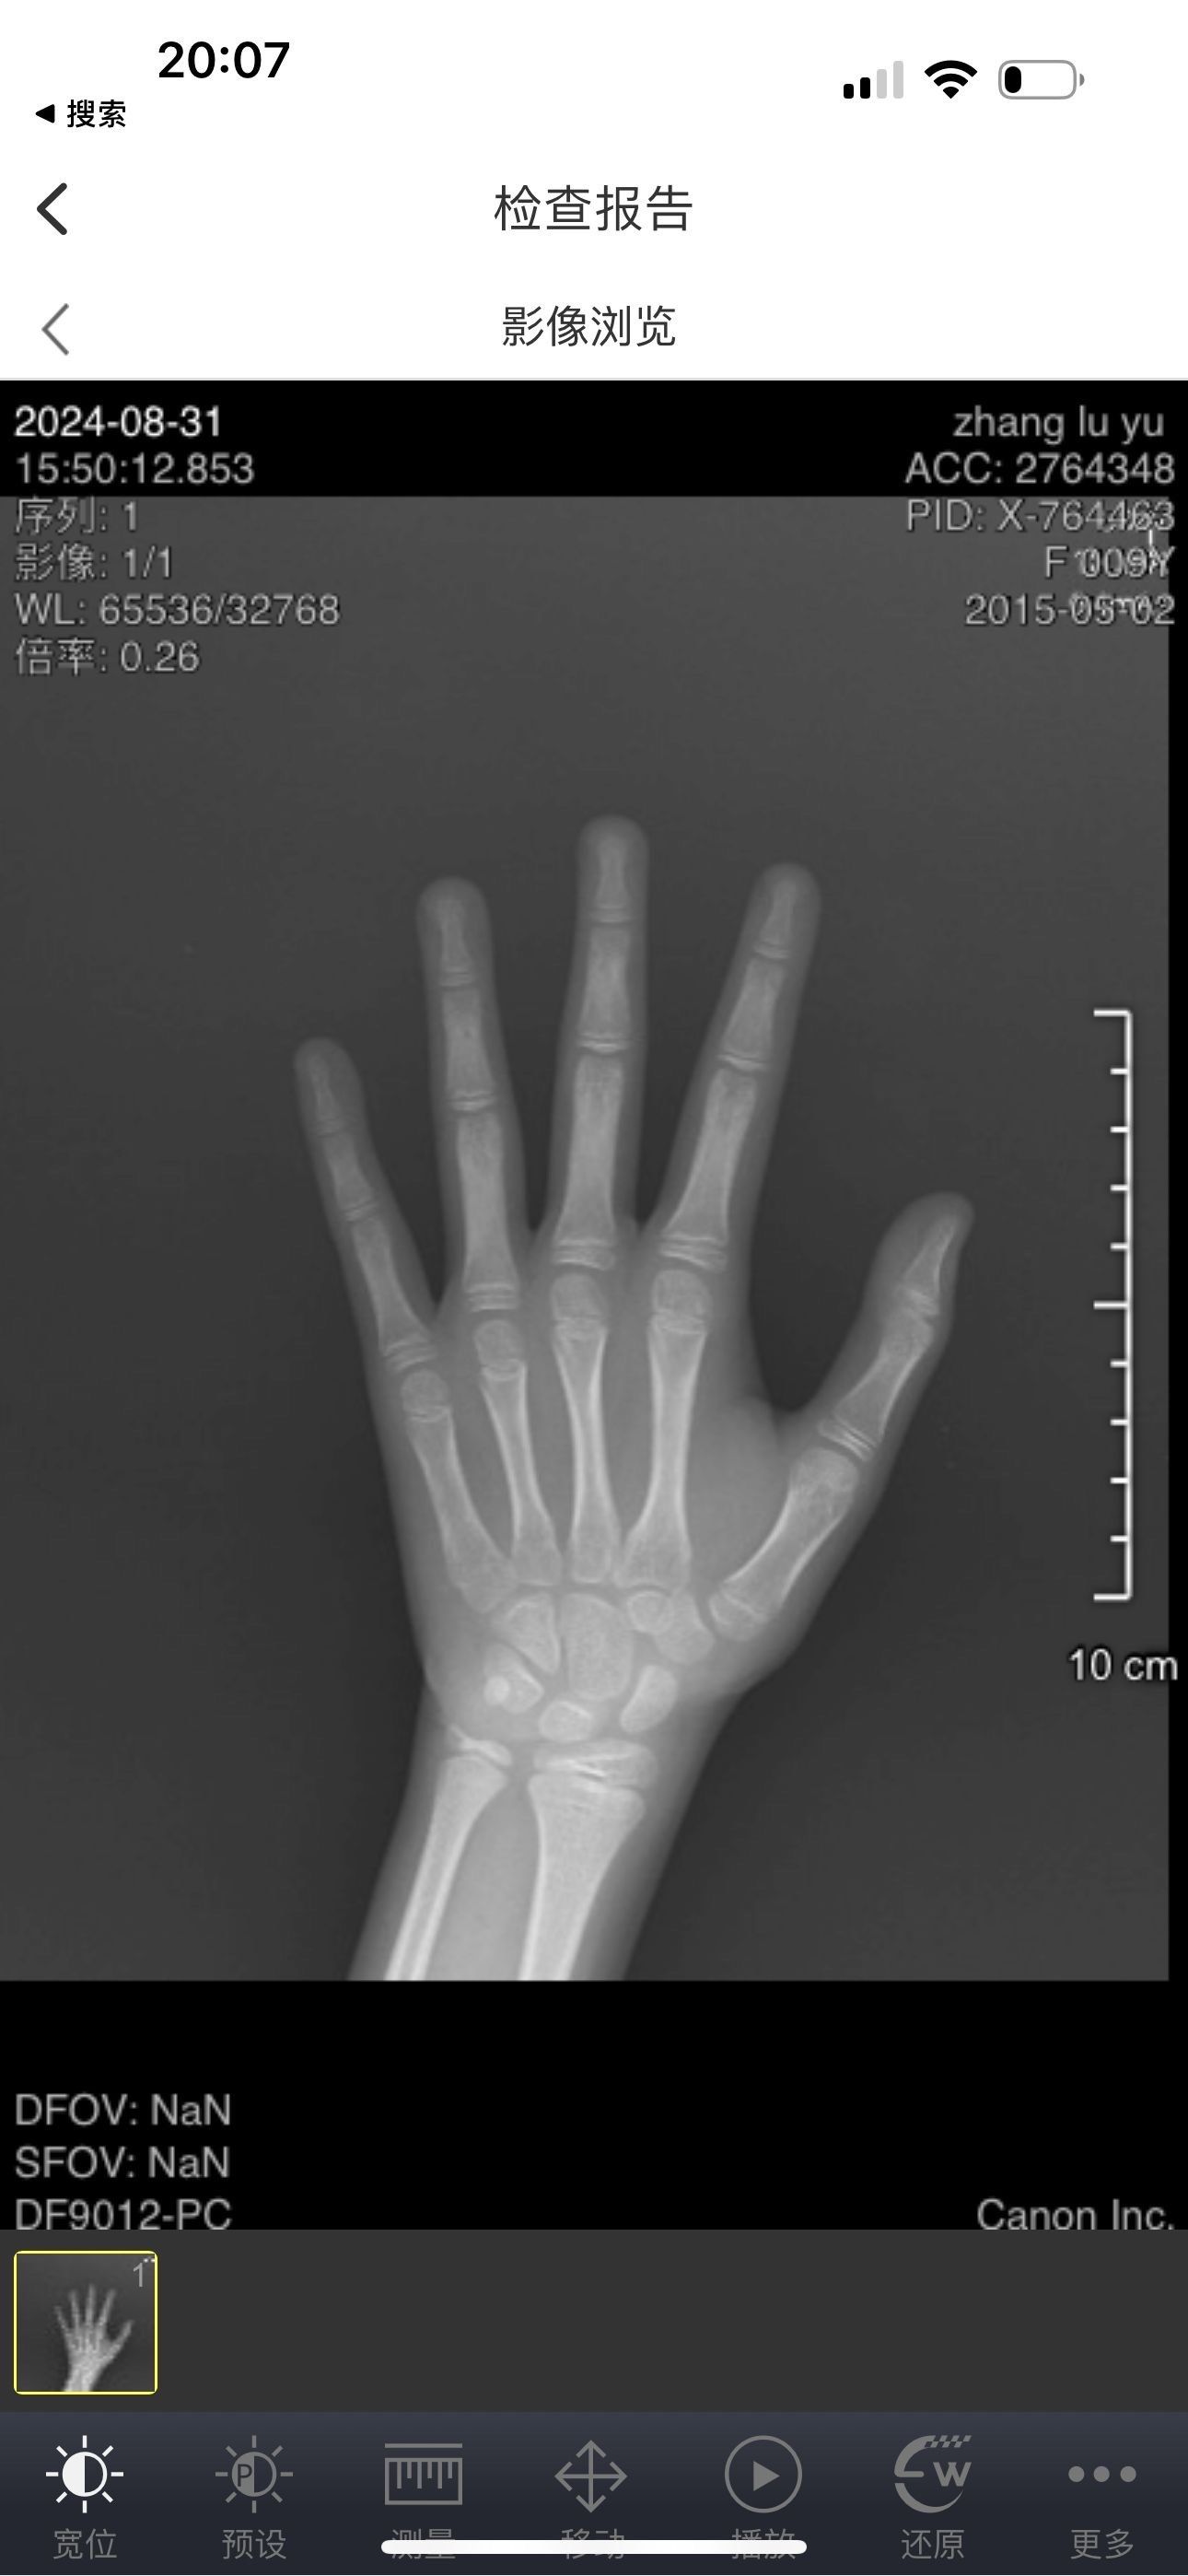

成人骨龄片

📖骨龄片读片全攻略:顺序与书写技巧